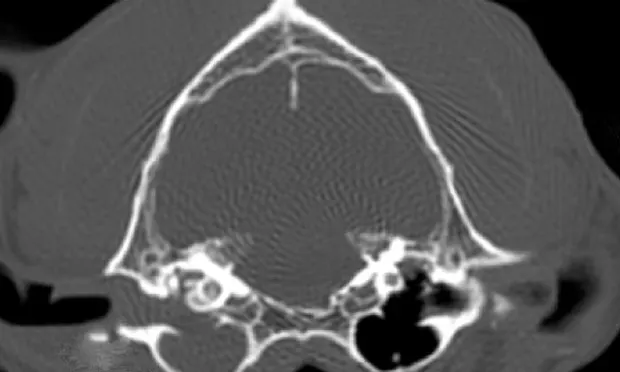

Cytology of the left ear showed too-numerous-to-count bipolar rods and degenerative neutrophils (Figure 1). A CT scan was recommended over radiographs because of its availability, the history of cutaneous lymphoma, and to rule out neoplasia of the ear canal (Figure 2). The CBC revealed a mild leukocytosis with mild neutrophilia and was consistent with a stress leukogram. Chemistry panel and urinalysis were within normal limits. Gentle deep ear flush was done repeatedly with warm saline to clear the exudate. The canal was erythematous, inflamed, and ulcerated, and the tympanic membrane was not visualized. Bacterial culture of the left middle ear exudate produced heavy growth of Pseudomonas aeruginosa. Following the deep ear flush, the left ear was reexamined with the video otoscope (Figure 3).

Interpretation and Treatment. Neurologic examination supported a peripheral origin of vestibular disease. Ear infection was suspected to be affecting the sensory receptors in the vestibular labyrinth and the vestibulocochlear nerve (cranial nerve 8). Although the clinical signs of vestibular disease were acute in onset, the otitis media was probably a chronic problem with no prior clinical signs. CT showed that the exudate extended from the bulla to the external meatus. The deep ear flush revealed no masses in the canal or bulla, and the exudate was removed. It was suspected that the organism was P. aeruginosa because of the bipolar-shaped rods and the nature and odor of the purulent exudate.